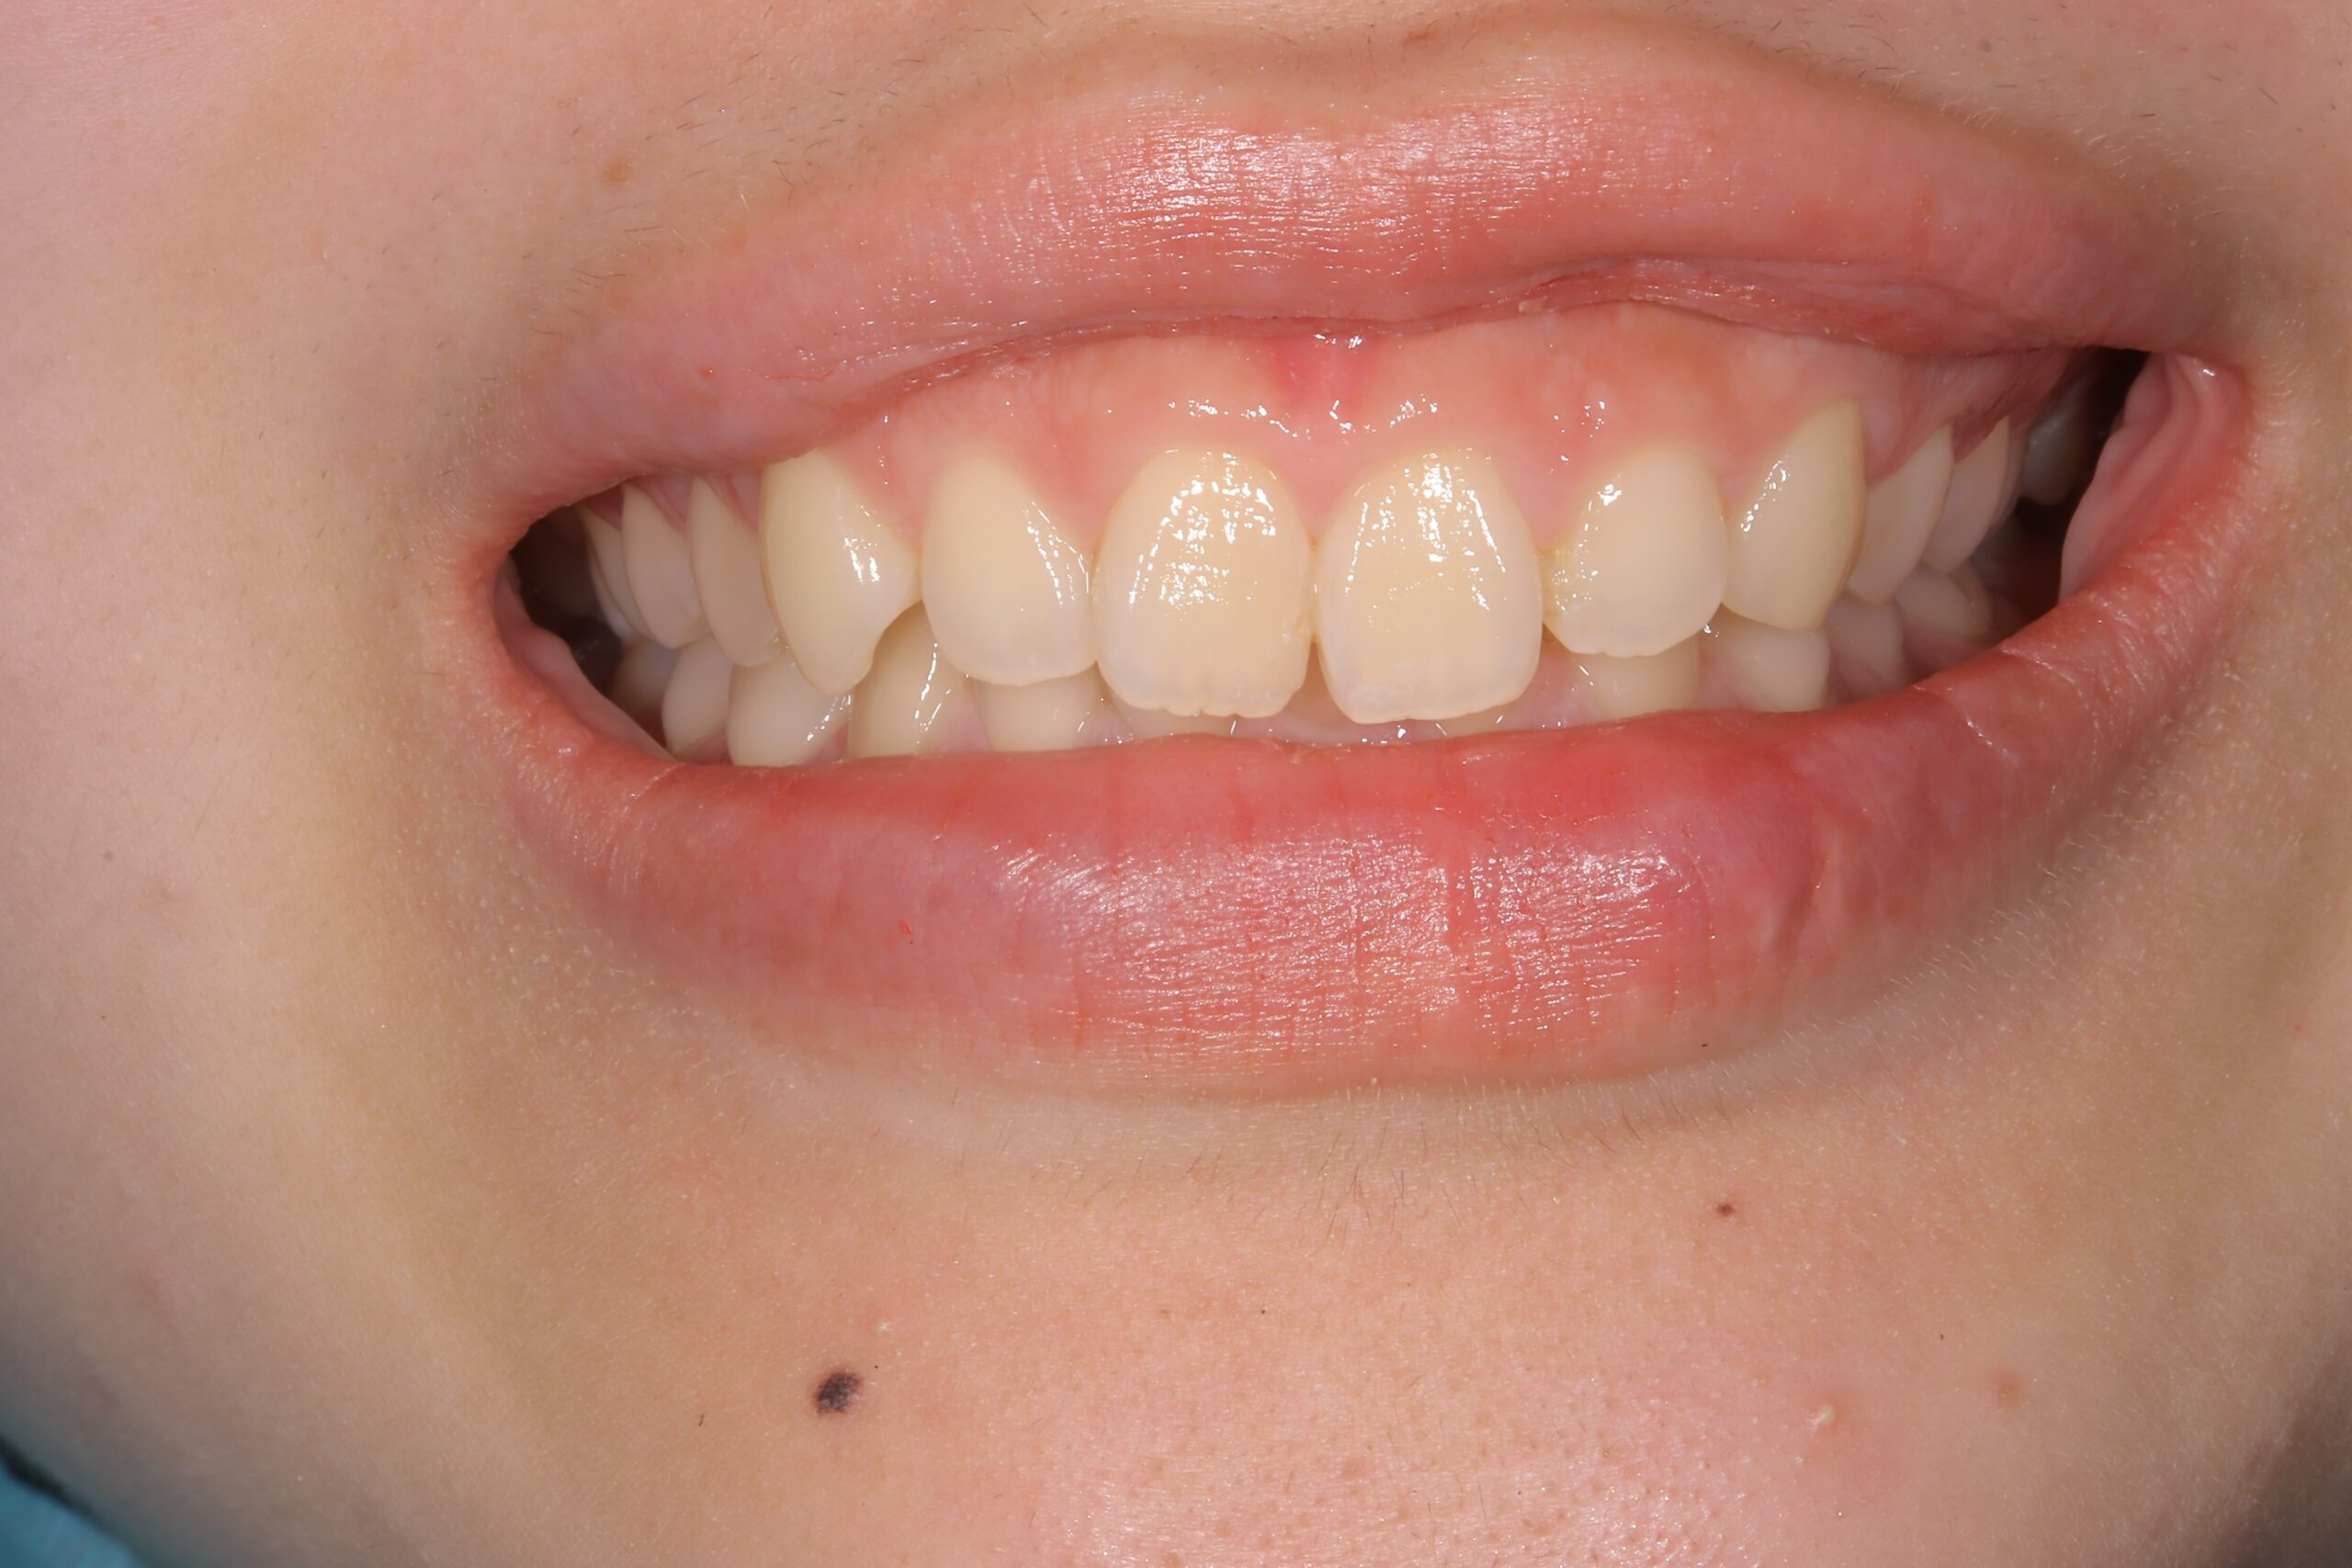

Before

ガミースマイル治療前の状態

術前

笑うと4ミリ歯ぐきが見えるガミースマイルです。

笑った時に3ミリ以上見える歯ぐきをガミースマイルと言い、人口の10%くらいの方がガミースマイルで悩まれている方は意外に多いです。シミュレーション用マウスピース